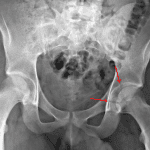

Age: 20

Sex: Male

Indication: Trauma

- Acute nondisplaced, mildly comminuted, transversely-oriented fracture of the left acetabulum

- Hips are located

- Transverse with posterior wall acetabular fracture

Acute nondisplaced, mildly comminuted, transversely-oriented fracture of the left acetabulum.

Hips are located.